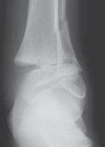

A B C D

TECH FIG 3•

Tillaux fracture treatment.

A,B.

Tillaux fractures are often not seen clearly on plain radiographic views, and it is important to obtain a mortise view to see the fracture fragment that is obstructed by the fibula in standard AP views.

C,D.

CT scans often aid in fracture characterization and operative planning.

E,F.

These fractures are fixed with compressive interfragmentary cancellous screws across the fracture site, without concern for transphyseal fixation as these patients are always

E F close to skeletal maturity.